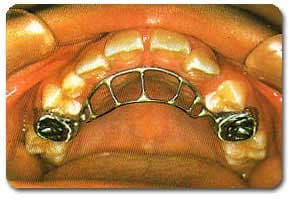

Habit Breaker یا عادت شکن جهت جلوگیری از مکیدن انگشت

فضا نگهدار چیست؟

فضا نگهدارندهها اسبابهای کوچکی هستند که از فلز یا مواد پلاستیکی ساخته شده و بخوبی با دهان بیمار تطابق مییابند. بیشتر کودکان ظرف چند روز اول با آن خود را وفق داده و به آن عادت میکنند.

فضا نگهدار چگونه به این کودکان کمک میکند؟

فضا نگهدارندهها باعث نگهداری و حفظ فضای حاصل از کشیدن دندانهای شیری، با ممانعت از حرکت دندانهای کناری به داخل آن میشوند و نهایتاً دندان دائمی جانشین شونده در سن مناسب و در جای خود رویش میکند. استفاده از این دستگاهها به منظور حفظ فضا، برای کودکان بسیار راحتتر و قابل قبولتر خواهد بود تا اینکه بعداً مجبور باشند با استفاده از دستگاههای ارتودنسی دندانها بجای خود هدایت شوند.